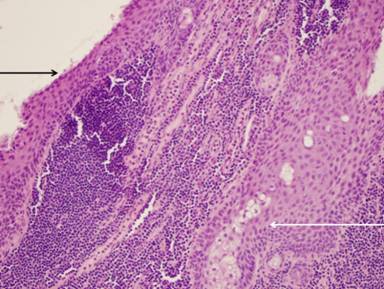

Surgical resection was recommended since a definitive diagnosis was not reached and, despite recovering from the fall, the patient continued to complain of vague epigastric abdominal discomfort. The patient underwent distal pancreatectomy and splenectomy. Macroscopic evaluation of the excised mass showed a 2.5 cm well-circumscribed, encapsulated cyst containing a central, friable brown material (Figure 2). Histologic evaluation revealed a pancreatic cyst lined by a stratified squamous epithelium with many benign sebaceous glands (Figure 3). No cellular atypia or mitotic activity was identified and there was no invasion of surrounding structures.

Figure 3. Photomicrograph of H&E stain at 20x magnification showing stratified squamous epithelium (black arrow), sebaceous units (white arrow), and surrounding lymphocyte infiltration. |